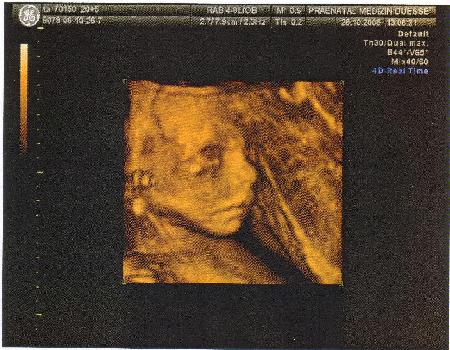

21.Woche